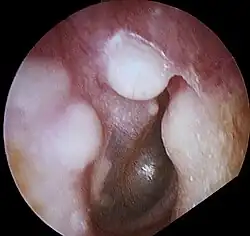

| Osteoma of external auditory meatus | |